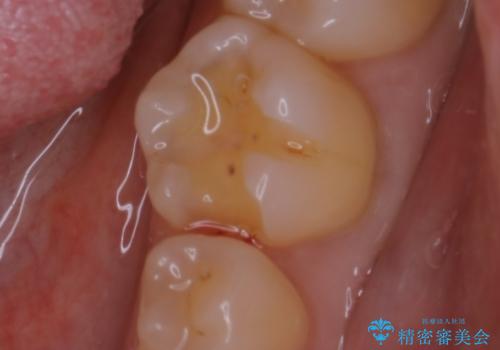

- 大きく口を開けると目立つ銀歯のやり替えをご希望された患者様です。適合のよいセラミックインレーで補綴することで、将来的な虫歯発生のリスクを最小限に抑え、機能面でも安心して使っていただけるようにしました

適合不良の補綴物は二次的な虫歯発生のリスクが高まります。

自費診療で用いられる材料は保険適応の材料に比べて、より精密で適合の良い被せ物作ることができるため、長期的な虫歯のリスクを大幅に減らすことが可能です。